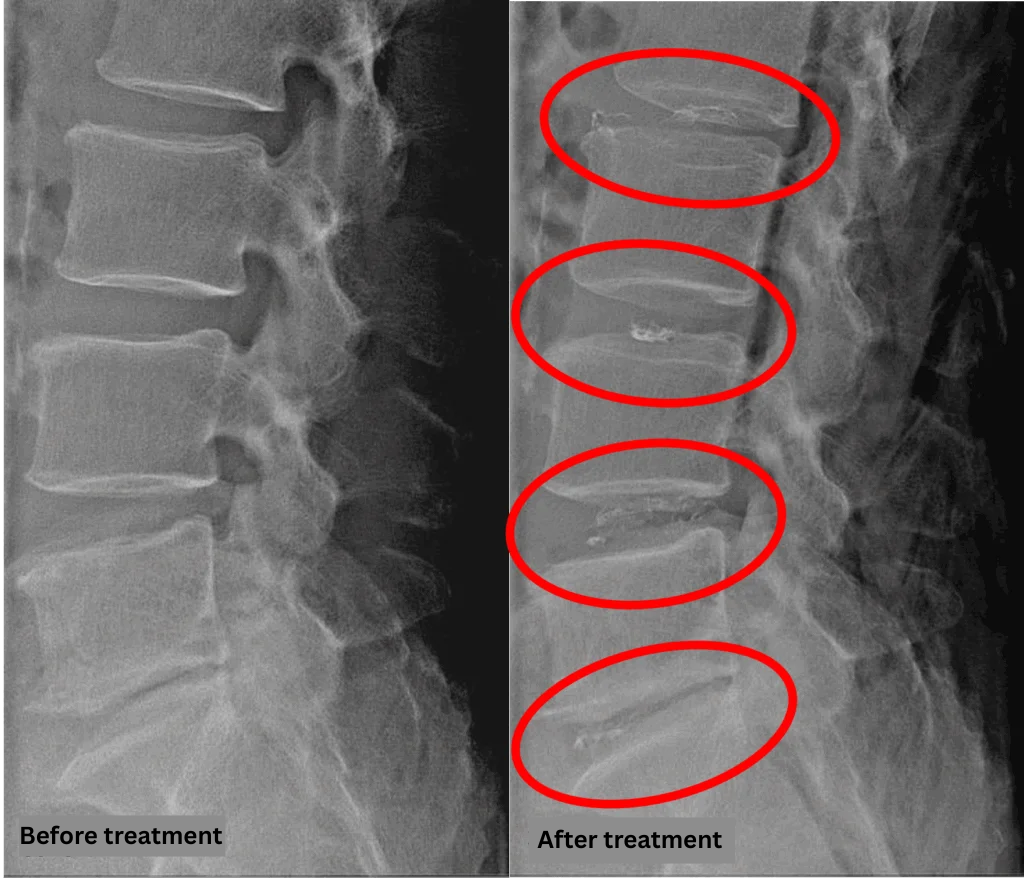

- L2/3, L3/4, L5/S: disc degeneration

- L4/5: disc degeneration and disc herniation

The above findings were also observed on the imaging.

These findings indicate that nerve compression at L2/3, L3/4, L4/5, and L5/S are likely the main causes of his symptoms.

After consulting with the patient, the Cellgel Method was performed on L2/3, 3/4, 4/5 and 5/s.